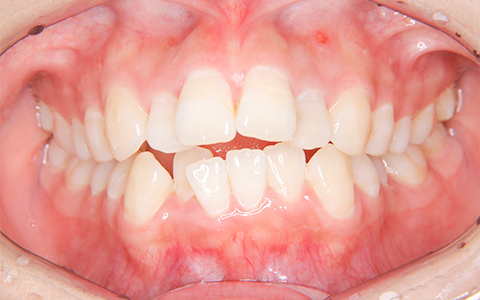

施術内容 上の2番目の歯が内側にあることがお悩みでご来院(33歳)。前歯部の叢生・交叉咬合に対するマウスピース型矯正装置(インビザライン)による非抜歯治療

治療期間 1年1ヶ月(通院7回)

費用 880,000円

リスク・副作用 歯が動く痛み、歯髄壊死、歯根吸収、歯肉退縮、リテーナーを使用しないことによる後戻り